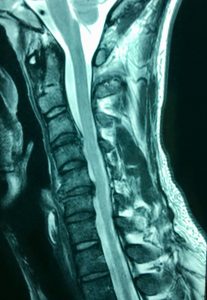

They continued by stating that if they had not met me they'd be lost and hopeless thinking nothing happened to his neck when he was suddenly kicked in the head during martial arts. This caused an obvious damage of at least two discs clearly shown on MRI. See image below.

This unfortunate male in his 3rd decade was kicked in the head in a sporting match.

The scan delineates extensive disc damage and his symptoms were clearly associated with all sorts of debilitating sympathetic effects and neurological symptoms which were starting to extend deeply into behavioural patterns. His life had become almost unliveable.

One of the doctors he saw was a specialist neurologist who advised that it was normal ageing.

"NORMAL AGEING"?

This stuff infuriates me. For one, degenerative discs at the high level are rare, and the traumatic history described the site of injury satisfactorily. Also, athletic, healthy men in their 20s do not suddenly think suicidal thoughts the month after being knocked unconscious and having to deal with constant pain.